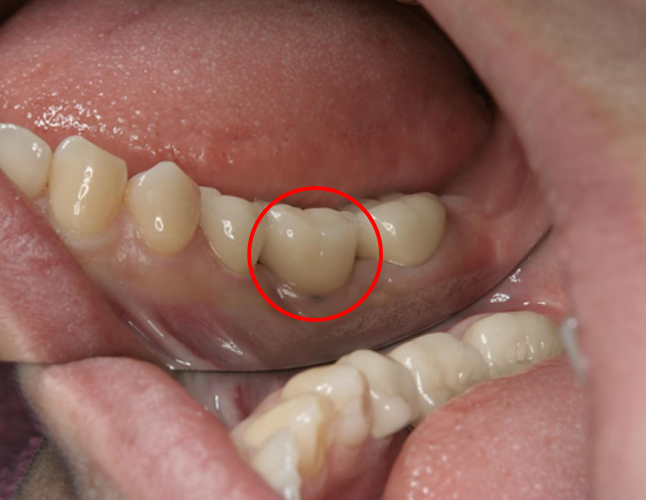

この患者さんは20台女性のまだ若い方ですが、下の奥歯が虫歯だったのを長く放置されていて悪くなり、残念ながら抜歯するしかなくなりました。

その後、骨にインプラントを埋めて、6週間後に歯型を取りセラミックの歯を作成、更にインプラント部位(赤丸部分)の前後の歯もセラミックで作成し装着しています。

このように、1本や2本だけ歯を失った場合には、最近ではインプラント治療も比較的短期間に終われる場合が多くあります。見た目も自然に仕上げることができますので、お気軽にご相談くださいね。